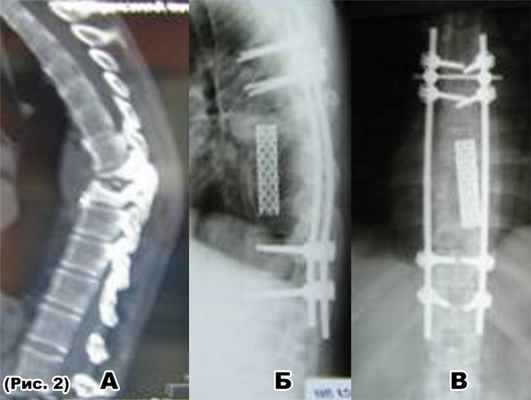

а) компрессионно-оскольчатый перелом Th4 позвонка со стенозом позвоночного канала;

б) декомпрессивно-стабилизирующая операция: спондилодез мешем с аутотрансплантатом;Th3-Th6, транспедикулярная фиксацияTh3-Th6 позвонков.

а) МРТ-переломовывихTh10 позвонка (стеноз п. к. 100%)